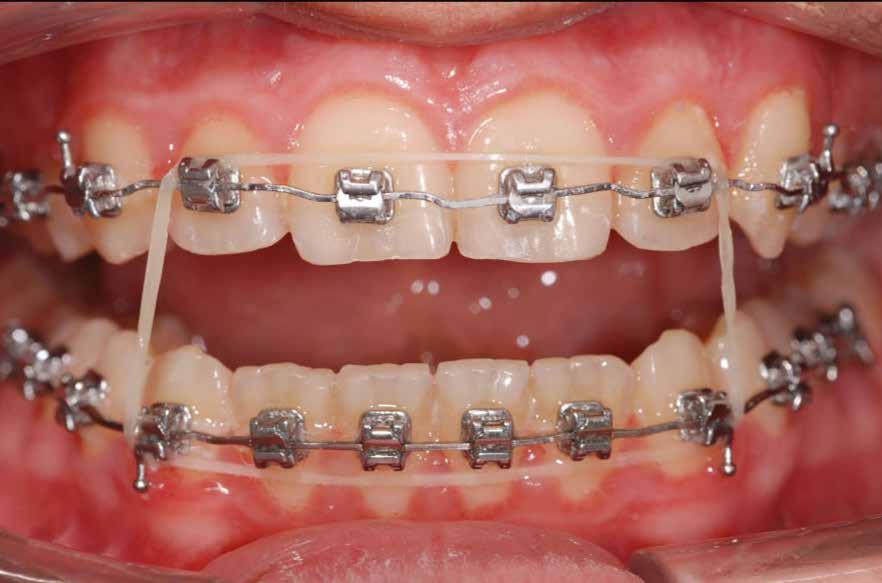

terséges harapásemelés pedig az alsó hatosokra, majd később a felső négyesekre került (8. kép). Az intermaxilláris elasztikus gumihúzás class-2-ess vektorú volt annak érdekében, hogy a disztálharapás korrekciója tökéletes legyen (9. kép). A harapást beállító elasztikus gumihúzásokat – mint minden kezelésnél –, ebben az esetben is folyamatosan, az egész kezelés alatt 24 órában (étkezések kivételével) viselte páciensünk.

A második Pitts-21 fix készülékes fázis ideje 16 hónap volt (10-12. képek)